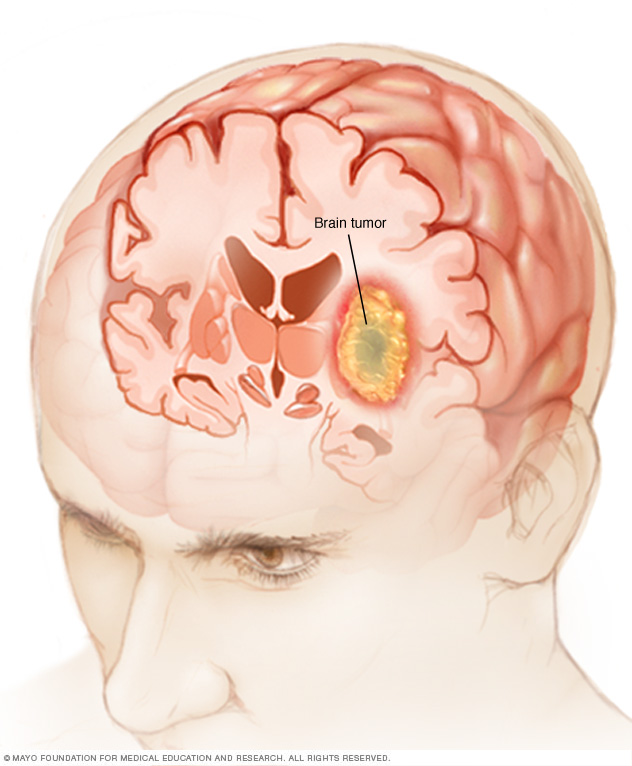

A brain tumor is a growth of cells in the brain or near it. Brain tumors can happen in the brain tissue. Brain tumors also can happen near the brain tissue. Nearby locations include nerves, the pituitary gland, the pineal gland, and the membranes that cover the surface of the brain.

Many different types of primary brain tumors exist. Some brain tumors aren't cancerous. These are called noncancerous brain tumors or benign brain tumors. Noncancerous brain tumors may grow over time and press on the brain tissue. Other brain tumors are brain cancers, also called malignant brain tumors. Brain cancers may grow quickly. The cancer cells can invade and destroy the brain tissue.

Brain tumors range in size from very small to very large. Some brain tumors are found when they are very small because they cause symptoms that you notice right away. Other brain tumors grow very large before they're found. Some parts of the brain are less active than others. If a brain tumor starts in a part of the brain that's less active, it might not cause symptoms right away. The brain tumor size could become quite large before the tumor is detected.